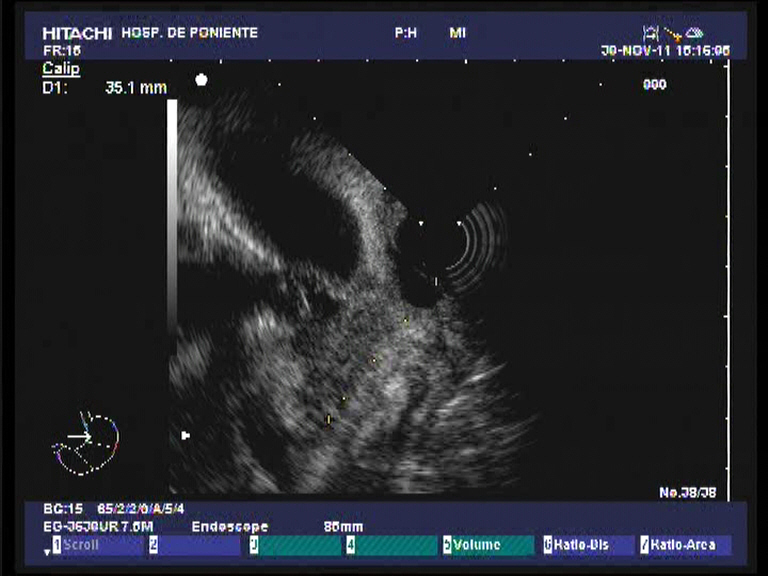

Paciente varón de 60 años de edad, sin antecedentes de interés que presenta dese hace un par de meses pérdida de peso importante (10 kgr), molestias epigástricas vagas junto a coluria e ictericia progresiva. Analíticamente destaca una BRT de 16 mgr/dl, a expensas de la fracción directa (8.21 mgr/dl), con ligera hipertransaminemia (GOT 68 UI/L, GPT 74 UI/L), GGT 1115 UI/L, FAT 558 UI/L e hiperlipemia mixta. El Ca 19.9 se encontraba a unos niveles de 242 UI/dl. Se practica una ecografía abdominal con el hallazgo de una masa en la cabeza pancreática de 3 x 2.7 cm, hipoecoica e irregular que obstruye el colédoco (dilatación retrógrada de unos 11 mm) junto a dilatación de la vía biliar intrahepática, vesícula dilatada (Courvoisier) sin adenopatias evidentes. El TAC trifásico realizado unos días después confirmando la existencia de la masa descrita a nivel de la cabeza pancreática (3 cm), que contacta con la pared duodenal, pero no infiltra la vena porta ni la VMS. Múltiples adenopatías de entre 5 y 1 cm adyacentes al tronco celíaco y peripancreáticas. Él colédoco y la vía biliar intrahepática se encuentran muy dilatadas, así como la vesícula biliar y el conducto pancreático. Con el diagnóstico de posible adenocarcinoma pancreático T3-N1-M0, se realiza una USE radial en nuestro centro, donde además de lo ya observado (la masa no obstante es de mayor tamaño 3.5 x 4 cm) en las anteriores pruebas diagnósticas, se confirma la infiltración de la VP y la confluencia con la VMS. El tronco celíaco y la AMS están libres de afectación tumoral. También se observaro varias adenopatías en el TC y peripancreáticas. Dado los niveles de BRT se decide colocar una prótesis biliar completamente recubierta por CPRE como drenaje biliar. Finalmente, para la confirmación histológica de la neoplasia, se realiza una USE-PAAF. El análisis citopatológico confirma la presencia de células malignas, aunque no se especifica la extirpe (quizás por la poca experiencia que aún se tiene en el estudio citológico).

El adenocarcinoma de páncreas es una neoplasia con muy mal pronóstico, incluso en los casos potencialmente resecables. Hoy día en el protocolo diagnóstico, además de la ecografía y TAC abdominal, se realiza una ecoendoscopia para valorar la afectación de las estructuras vasculares vecinas (sobre todo venosas) y completar el estadiaje tumoral. El sistema mas utilizado es el «American Joint Committe on Cancer 2003 TNM Clasification for Pancreatic Cancer». Según éste. el caso presentado sería un T3-N1-M0 (estadio IIB). En esta clasificación, la irresecabilidad viene marcada por la presencia de la invasión vascular de la AMS y el TC y sus ramas (como la arteria gastroduodenal), pero la realidad demuestra que en la mayor parte de los casos, el tamaño tumoral > 3 cm, la invasión de la pared duodenal y la infiltración portal-VMS conjuntamente también suelen implicar irresecabilidad cuando se realiza la laparotomía. Por otro lado, la USE aunque valora muy bien la invasión de la VP (S: 80 %) y vasos esplénicos, falla algo mas en el análisis de invasión tumoral de la VMS (resultados de S variables según las series, del 17-80 %) y AMS (S: 17 %). Es difícil visualizar todo el recorrido de estos vasos por ecoendoscopia ante la presencia de un tumor de gran tamaño en el proceso uncinado o de la porción inferior del páncreas. Quizás el TAC trifásico es superior (incluso RMN) para valorar estos vasos. La conclusión final es que hay que hacer ambas técnicas en el estudio de extensión. Otra cuestión controvertida es realizar o no PAAF por ecoendoscopia en todos los casos (algunos hospitales los restringen a los pacientes irresecables por el temor a la diseminación de las células malignas el el trayecto de la punción). Muchos centros la hacen de forma rutinaria como en nuestro caso. Y por último, otra cuestión es si aquellos pacientes con ictericia obstructiva con neoplasias de páncreas potencialmente resecables, se benefician de un drenaje biliar por CPRE. Los últimos estudios sugieren que aquellos enfermos con cifras de BRT > 15 mgr /dl deberían ser drenados porque los resultados en cuanto a morbi-mortalidad quirúrgica son mejores.